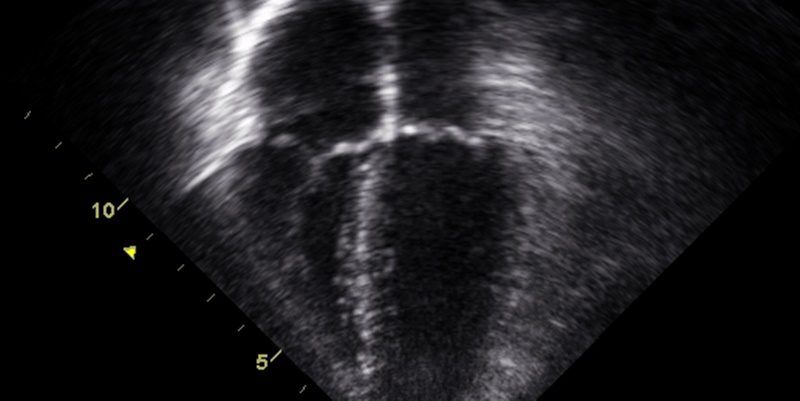

FTTE is a point-of-care ultrasound tool that allows clinicians to rapidly assess cardiac function at the bedside. In the context of post-CS ICU admissions, FTTE helps differentiate between cardiac and non-cardiac causes of shock and respiratory distress—conditions that often masquerade as routine postpartum changes. By offering real-time, non-invasive insight into the heart’s status, FTTE enables targeted interventions, potentially saving lives.

This prospective, observational cohort study included 60 post-CS patients admitted to the ICU within 42 days of delivery at a tertiary care center. FTTE was performed in patients with suspected cardiac disturbances, unresolved clinical dilemmas, or significant hemodynamic or respiratory instability. Cardiology residents, using advanced ultrasound equipment, performed the scans. FTTE findings were used to confirm, refine, or rule out cardiac pathologies and guide subsequent management.